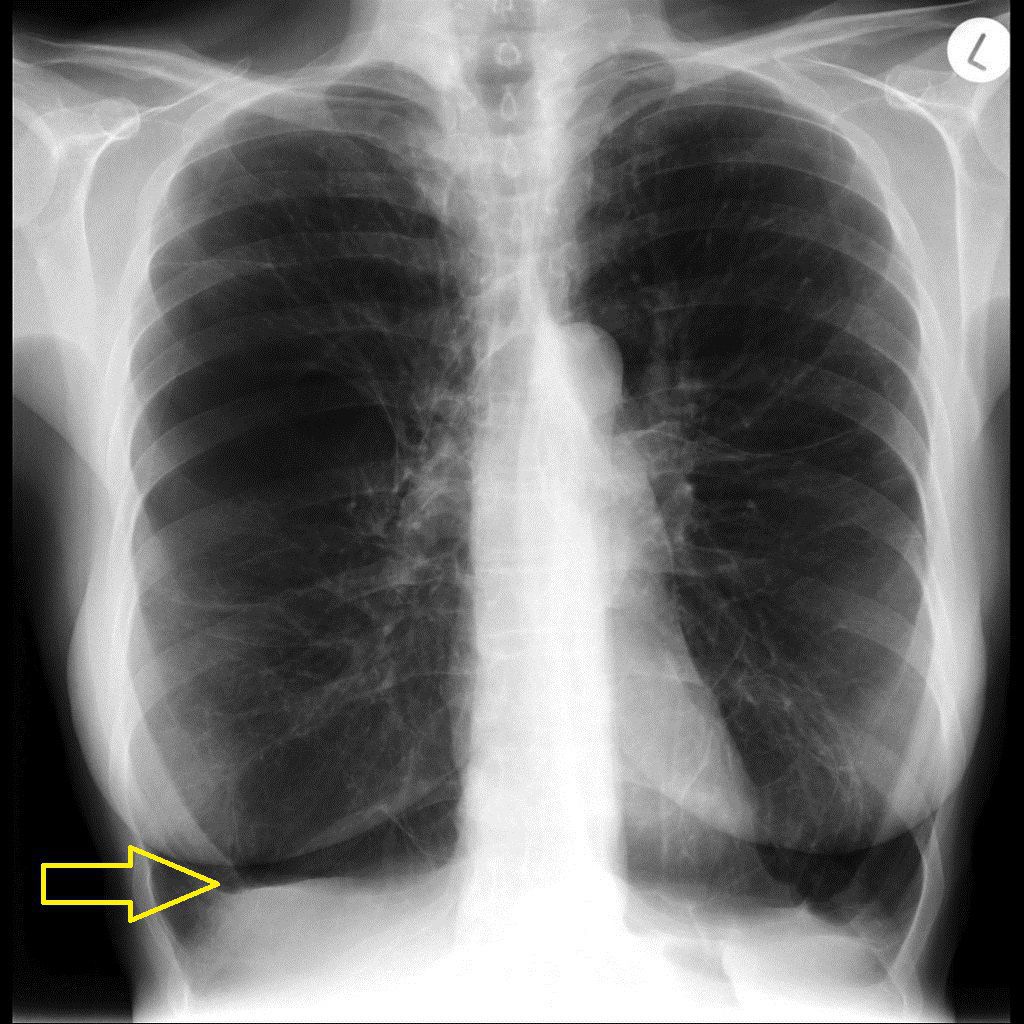

The main constituents of Chronic Obstructive Pulmonary Disease (COPD) are chronic bronchitis and emphysema. Characteristic radiological findings may be demonstrated in such patients. Following characteristics can be appreciated in case of emphysema: - Hyperinflated lungs - Flattened hemidiaphragms - Small-sized heart - Bullous changes - Saber-sheath trachea (coronal narrowing of trachea on frontal view but sagittal narrowing on lateral view) Reference: https://radiopaedia.org/articles/chronic-obstructive-pulmonary-disease-1 Image via: https://www.wikidoc.org/index.php/Alpha_1-antitrypsin_deficiency_x_ray